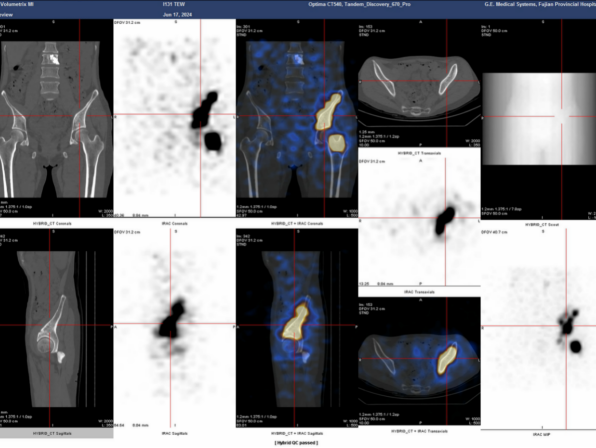

▲治疗后碘131SPECT/CT融合断层扫描图像